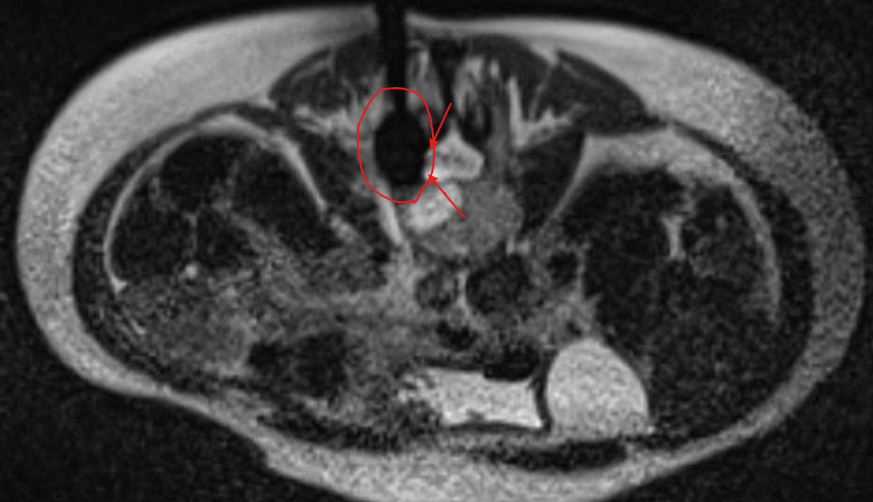

MRI Guidance - our newest frontier for unparalleled soft tissue targeting and radiation-free interventions

MRI Guided Cryoablation

Unlocking the power of ICE with the precision of MRI